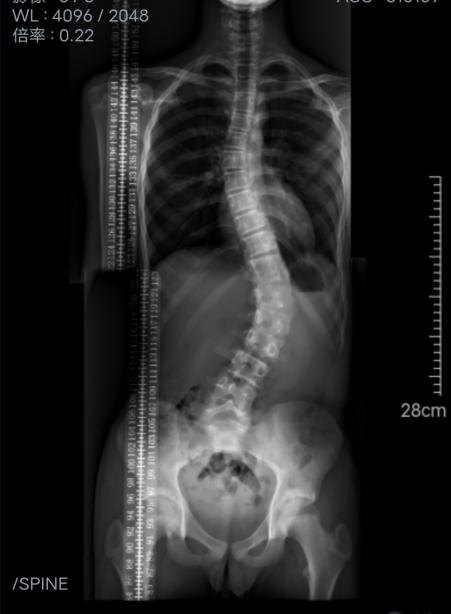

蒋晶飞马上对小帅进行仔细的体格检查,经过脊柱拍片、测量,发现小帅的脊柱腰段侧弯46°,保守治疗已经无法纠正,在邀请广州医科大学附属第三医院大外科主任、骨科主任兼脊柱外科主任吴增晖教授会诊后,建议手术治疗。小帅父母在充分了解病情、预后等情况后,也同意并接受手术治疗方案。最后通过骨伤科积极充分的术前准备,小帅的手术非常成功,目前正在进行术后的康复训练,术后恢复良好。